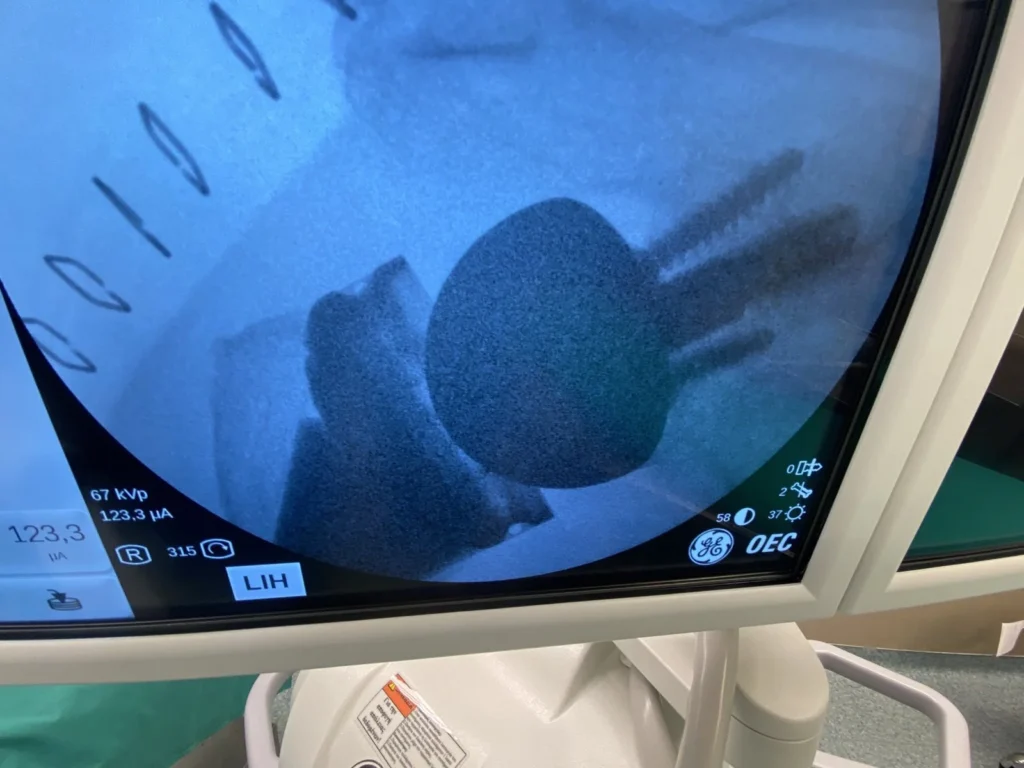

Ξεκίνησε σαν μια απλή ενόχληση. Οι πρώτες σκέψεις είναι πάντα οι ίδιες: ίσως να έγινε από κάποια απότομη κίνηση, μπορεί